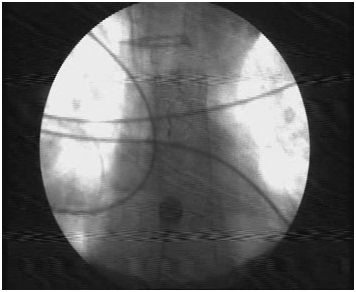

Figure 2 X ray view of Dannis Ella stent in situ.